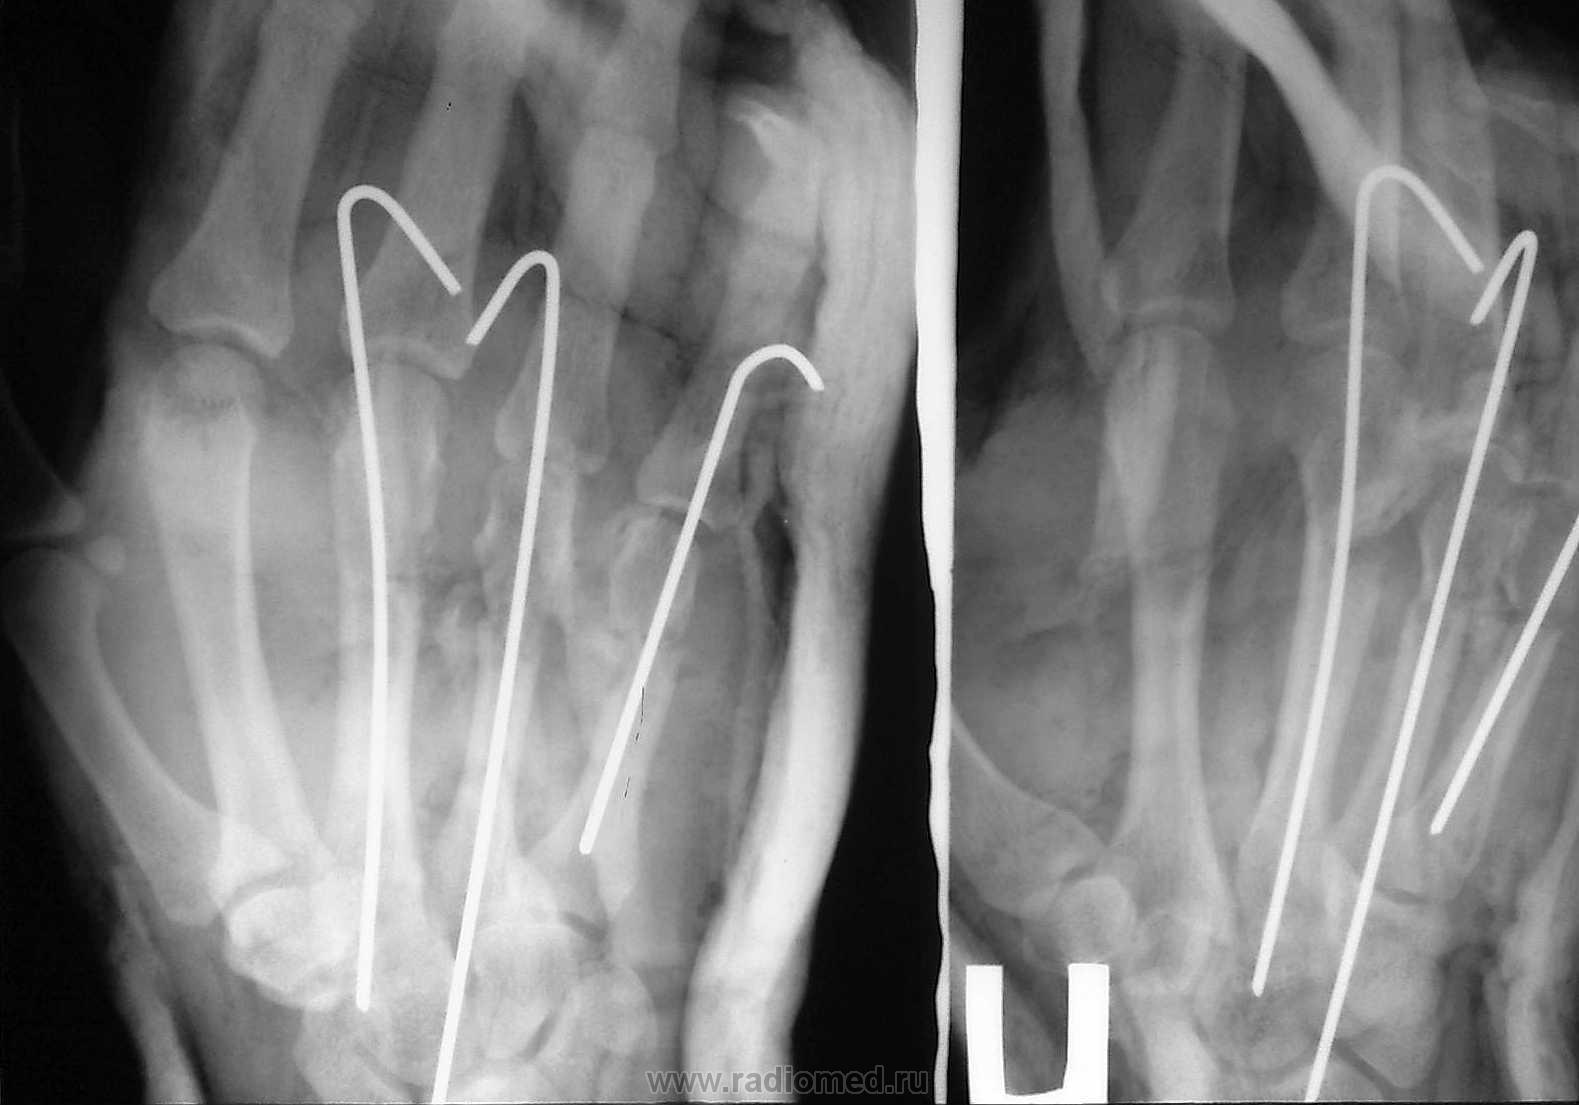

Очередной случай

По большому счету, это уже набор изображений, характеризующих определенный профессиональный травматизм, а данная тема становится актуальной, не только в плане диагностики, но и в векторе вопросов техники безопасности, возможно даже на производстве.